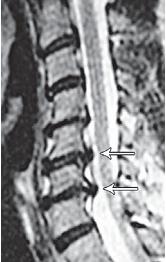

![]() На рентгенограмме № 4 изображен межпозвонковый сегмент в далеко зашедшей стадии дегенерации. Спондилёз второй степени в сочетании со снижением межпозвонкового промежутка говорит о том, что в прошлом на данном уровне имелась протрузия межпозвонкового диска, которая была стабилизирована развившейся стадией фибротизации поражённого диска (что хорошо видно на МРТ № 37). Бывает, что спондилёз может травмировать эпидуральную клетчатку (при движении позвоночника), в результате чего в ней возникают асептические воспалительные процессы. Эпидуральная клетчатка со временем уплотняется, склерозируется, в ней появляются фиброзные тяжи, которые могут деформировать спинномозговой корешок, вызвать его натяжение или сдавление. А при значительном увеличении (разрастании) спондилёза может развиться стеноз спинномозгового канала второго типа (первый тип стеноза — врождённый, второй — приобретённый), что довольно часто бывает при срыве адаптивных механизмов во время развития дегенеративно-дистрофических процессов в межпозвонковых дисках. Рентгенограмма № 5 ![]() МРТ № 38 ![]() На рентгенограмме № 5 шейного отдела позвоночника — выраженный спондилёз третьей степени и остеофитоз, что хорошо видно на МРТ № 38 сегментов шейного отдела позвоночника. В целом можно сказать, несмотря на то что спондилёз и остеофиты являются следствием определённых заболеваний позвоночника и в некоторой степени способствуют биомеханическим нарушениям в других сегментах позвоночника, всё же они небесполезны. Во многих случаях это своеобразная «скорая помощь» организма в ответ на невозможность осуществить полноценную регенерацию повреждённого позвоночно-двигательного сегмента. Данные костные наросты хоть и ограничивают движение сегмента, но тем самым предупреждают и замедляют его дальнейшее разрушение. Так что если при обследовании позвоночника у вас обнаружат спондилёз или остеофиты, то не стоит бояться этого диагноза. На самом деле всё не так страшно, как кажется на первый взгляд. Рентгенограмма № 6 ![]() МРТ № 39

На рентгенограмме № 6 поясничного отдела позвоночника выраженный остеофитоз, спондилёз третьей степени, что также хорошо видно на МРТ № 39 поясничного отдела позвоночника МРТ № 40 ![]() МРТ № 41